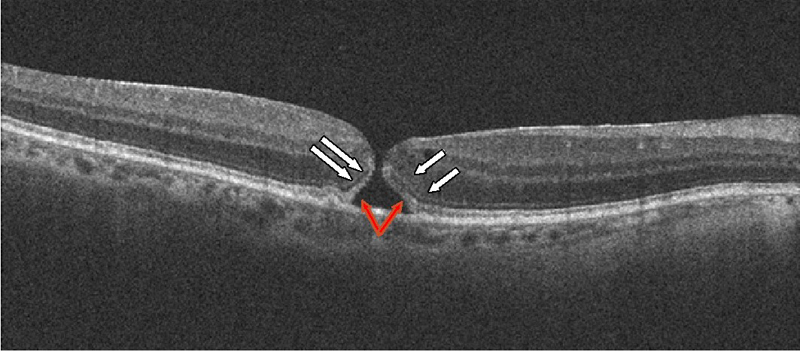

La OCT permite diferenciar con claridad el agujero macular de grosor completo de otras patologías que pueden ser similares en la exploración funduscópica, como los agujeros lamelares y los pseudoagujeros. La exploración con OCT muestra un defecto de todas las capas de la retina.

En formas recientes de agujero macular puede verse conservación de la capa elipsoide y de la membrana limitante interna en los bordes del agujero (

Figura 7). En formas con una mayor cronicidad suele perderse la integridad de la capa elipsoide y de la membrana limitante externa, aparece un levantamiento de los bordes con un edema quístico en los márgenes del agujero y se aprecian alteraciones del epitelio pigmentario (

Figura 7. Agujero macular de reciente aparición. Se objetiva un defecto completo de todas las capas de la retina. Es posible apreciar con claridad la membrana limitante interna (flechas blancas) y la capa elipsoide (flechas rojas) en los márgenes del agujero.

Figura 8. Agujero macular crónico. Se aprecia un levantamiento de los bordes del agujero, con edema quístico. En los márgenes del agujero no pueden diferenciarse la membrana limitante interna y la capa elipsoide.